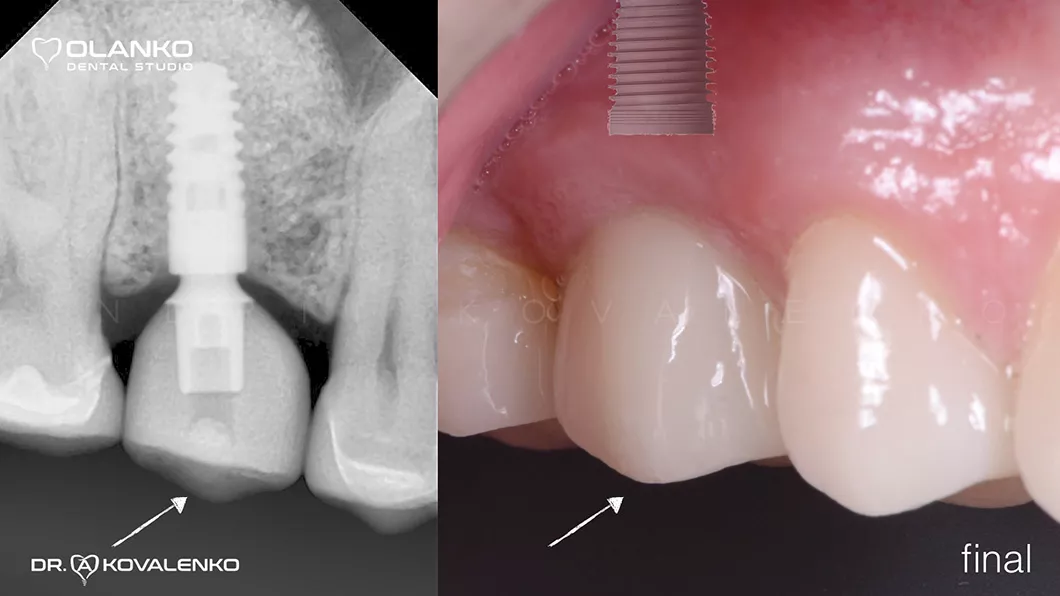

Ситуація після встановлення коронки ДО / ПІСЛЯ

Ситуація після встановлення коронки ДО / ПІСЛЯ Оланко Бровари Київ